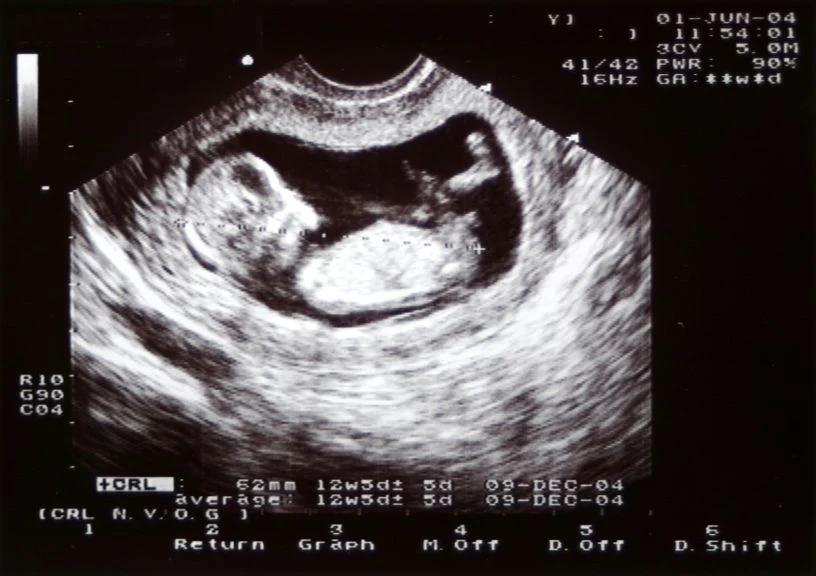

Gibt es eine Möglichkeit, das GA meines Kindes zu überprüfen?

Es gibt verschiedene Methoden, um das GA Ihres Kindes zu überprüfen. Ihr Arzt kann eine Ultraschalluntersuchung durchführen, um das GA Ihres Kindes zu bestimmen.